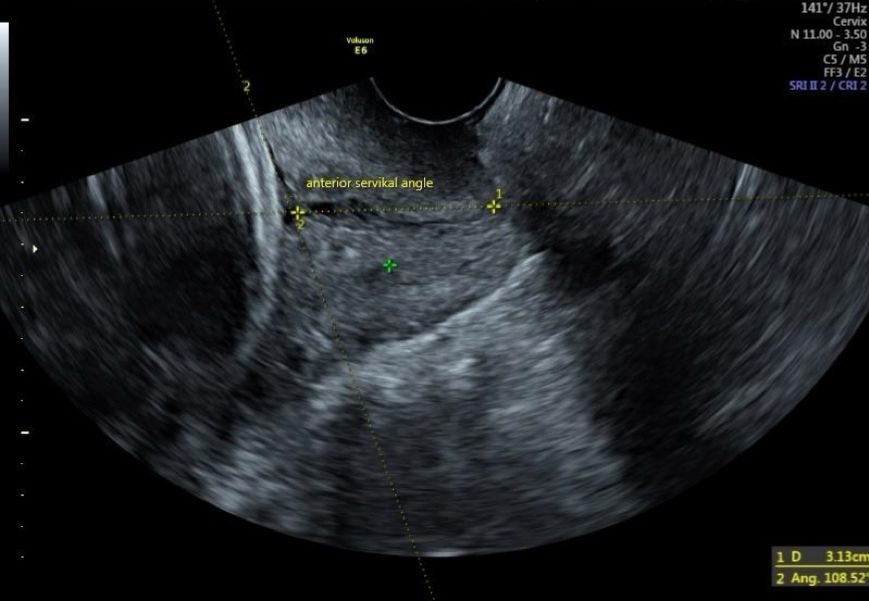

To ensure standardization of the study, measurements and examinations were performed by a single physician using the same ultrasound device (Voluson S10 BT18 5788346). First, fetal biometric measurements were taken using the transabdominal probe of the ultrasound. Then, the transvaginal probe was used to measure cervical length, uterocervical angle, and posterior cervical angle, which were recorded. Vaginal examination was performed to assess cervical dilation, effacement, and Bishop score. With the patient in the lithotomy position and empty bladder, care was taken to avoid applying pressure to the cervix with the transvaginal probe. The cervix was aligned in the midline, and the endocervical canal was visualized throughout its length. During cervical measurement, care was taken to ensure that the internal os, external os, and entire endocervical canal were visible in the same image. The distance between the external os and internal os was recorded as the cervical length. With the endocervical canal, external os, and internal os linearly displayed on the screen, the angle between the endocervical canal, anterior uterine segment, and posterior uterine segment was measured using the ultrasound's “angle measurement” feature. For the measurement of the uterocervical angle, the first line of the angle was defined along the endocervical canal used for measuring cervical length, and the second line was drawn from the internal os along the anterior uterine segment for a minimum of two centimeters. The angle between these two lines was recorded as the uterocervical angle in the form (Figure 1). When measuring the posterior cervical angle, the line extending along the endocervical canal and the line with a minimum length of two centimeters drawn between the cervix and the posterior uterine segment were taken as basis and the angle between the two was recorded as the posterior cervical angle (Figure 2).

Figure 1. Uterocervical angle (UCA).